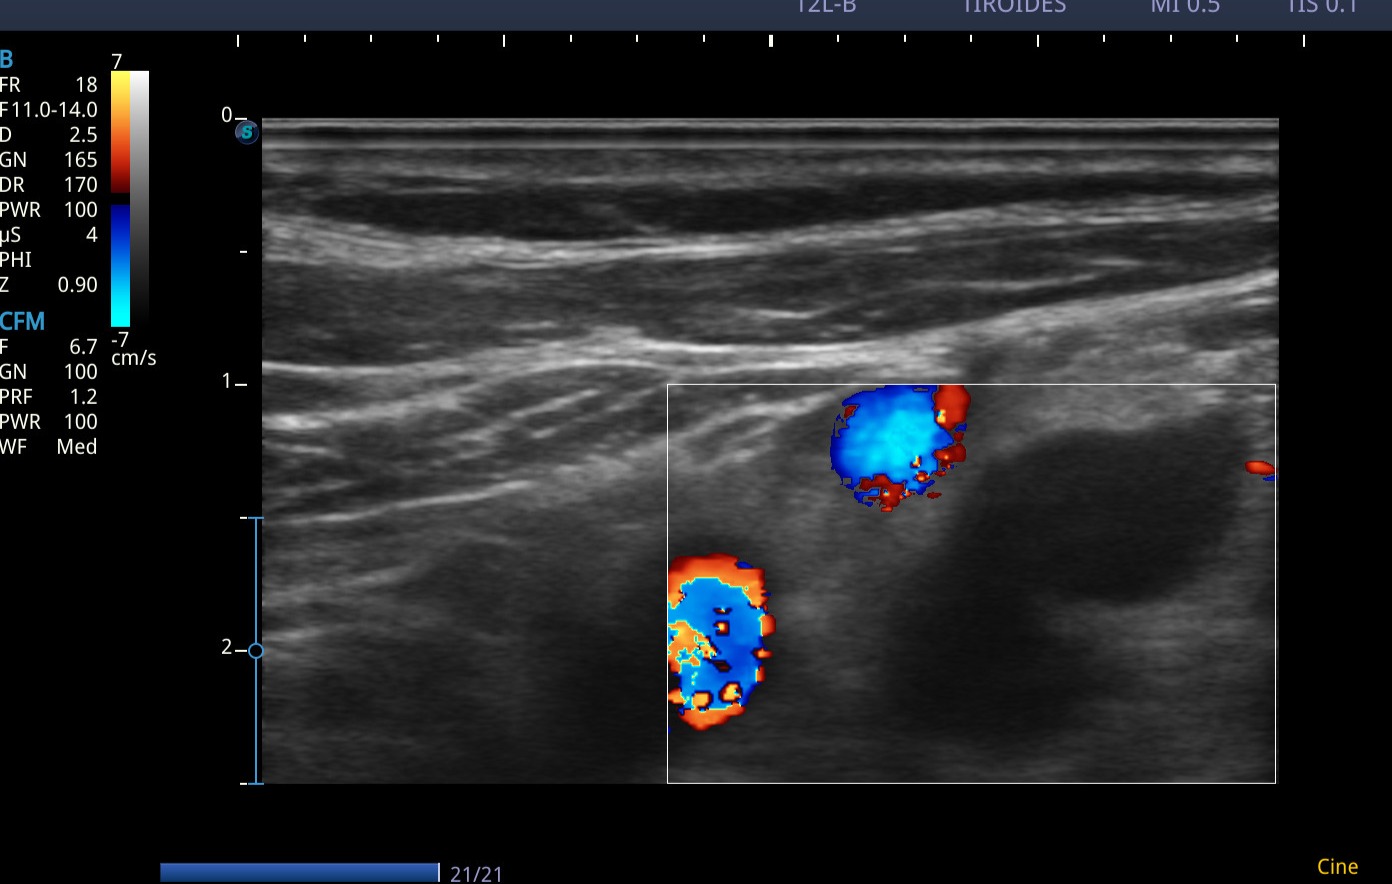

En las imágenes ecográficas del centro de salud se visualizan los siguientes hallazgos:

Conglomerado adenopático en cadena ganglionar laterocervical izquierda. Los ganglios visualizados presentan márgenes poco definidos/irregulares, ausencia de hilio ecogénico, ecogenicidad heterogénea, y algunos con forma redondeada, características con alta sospecha de malignidad. Dadas tales características y antecedentes personales, se deriva de forma preferente a Medicina Interna, para completar estudio de adenopatías.